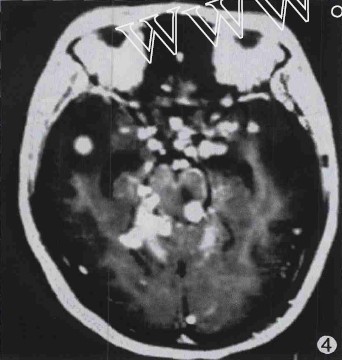

图4 鞍上池、环池、双侧裂池结节状脑膜强化。

2.2 结核瘤并发结核性脑膜炎20例,3例粟粒性脑结核均同时伴有结核性脑膜炎;其中16例基底池脑膜增厚伴基底池闭塞,12例同时伴有环池及侧裂池狭窄或闭塞;4例大脑凸面脑膜增厚,2例伴梗阻性脑积水,7例显示双侧大脑中动脉狭窄。增强扫描示脑膜呈条状、斑块状或结节状强化;3例脑基底部脑膜呈串珠样小结节强化,强化方式以蛛网膜-蛛网膜下腔强化为主;3例同时伴有硬脑膜-硬膜下强化。